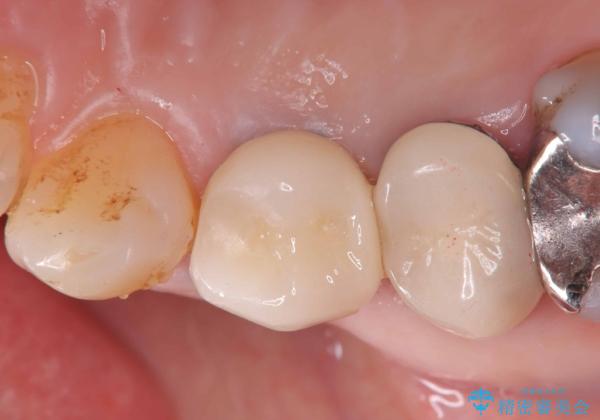

抜歯後、骨が出来るまで6ヵ月待ちその後インプラントを埋入しました。

アバットメントは患者様の歯肉に合わせて作製するカスタムアバットメントを入れ被せ物はオールセラミッククラウンで被せています。

メタルコアは度々歯根破折の原因になります。なので現在はファイバーコアが主流となっています。